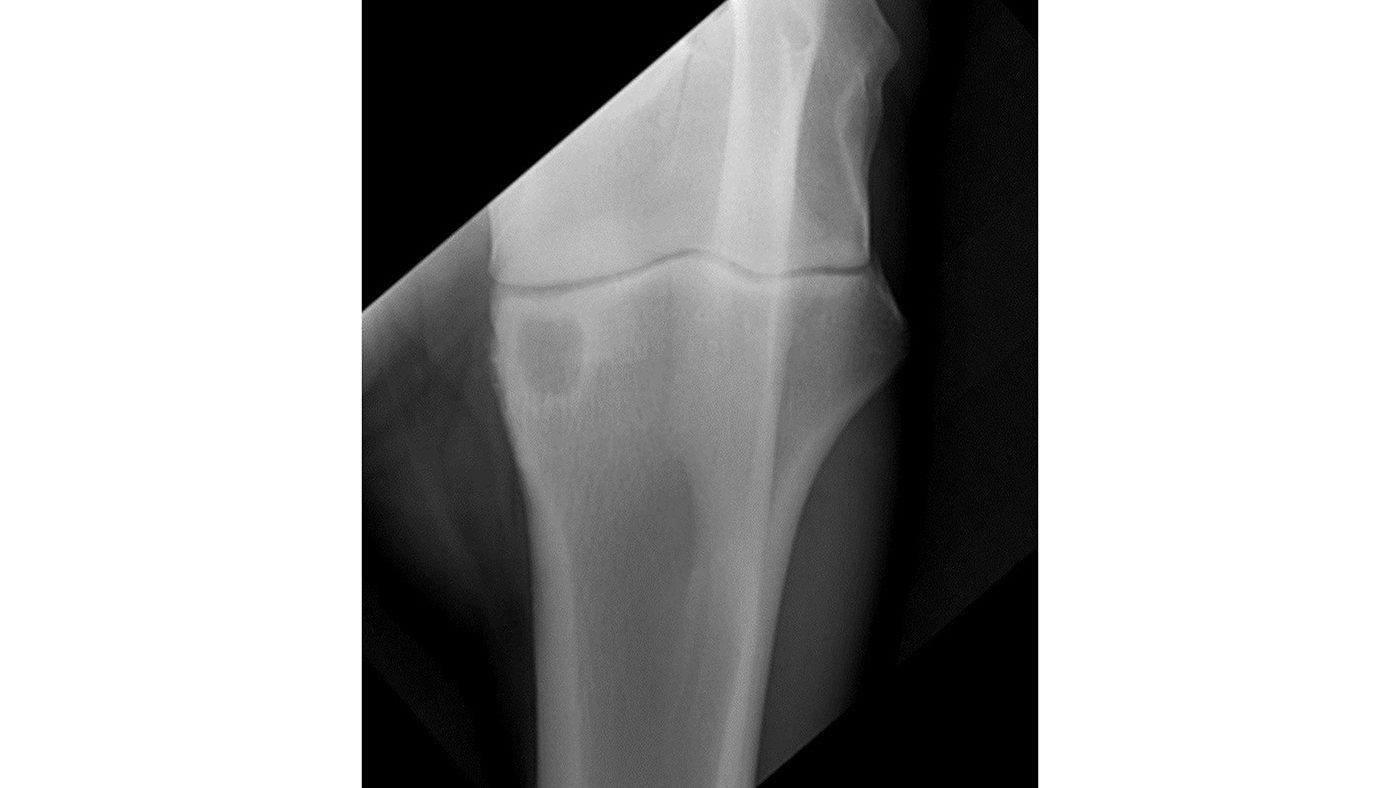

A review of normal radiographical variants commonly mistaken for

UK Vet Equine Diagnosis and management of traumatic equine fractures Elbow Hygroma Horse capped elbow and capped hock are inflammatory swellings of subcutaneous bursae in horses. shoe boil, olecranon bursitis, elbow hygroma. — if you have ever seen a horse with a large, movable swelling at the point of the elbow, it is likely a capped elbow. • it is typically as a result of trauma to the. Direct trauma,. Elbow Hygroma Horse.

Fractures of the Elbow in Horses Musculoskeletal System Merck Elbow Hygroma Horse olecranon bursitis is also known as capped elbow, elbow hygroma, or shoe boil. — if you have ever seen a horse with a large, movable swelling at the point of the elbow, it is likely a capped elbow. — olecranon bursitis, also identified as elbow hygroma, is an inflammation of the bursa characterized by marked swelling near. Elbow Hygroma Horse.